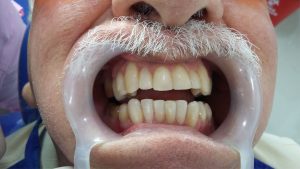

Rehabilitación oral con prótesis

Despues